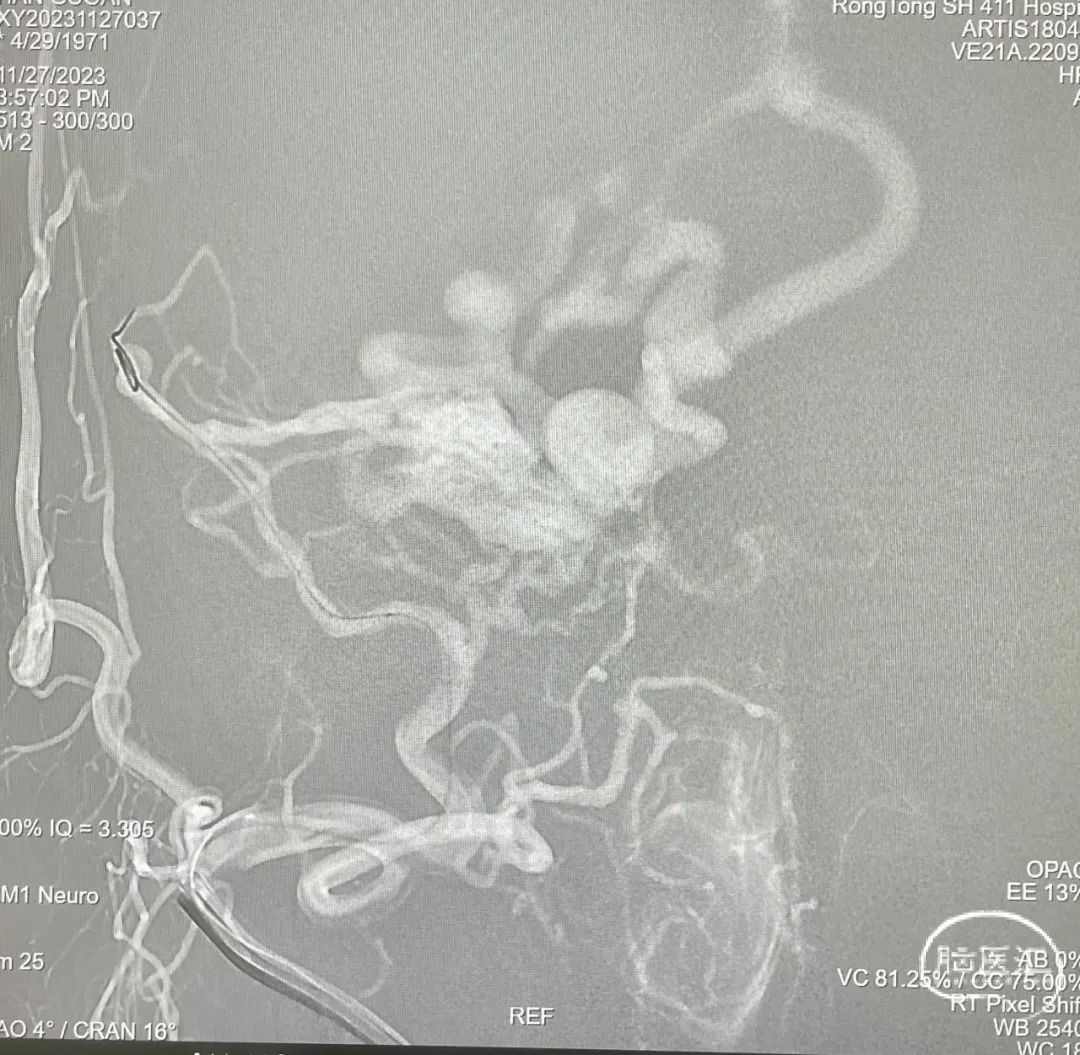

选取工作角度,正侧位造影

Echelon-10微导管在ASAHI 0.010微导丝导引下经右侧脑膜中动脉分支超选至瘘口,可见瘘口口径大,微导管直接越过瘘口,进入引流静脉起始部。

Marathon微导管在ASAHI 0.010微导丝导引下经右侧脑膜中动脉分支超选至瘘口近端。

经Marathon微导管手推造影明确微导管位于瘘口动脉端,Echelon-10微导管位于瘘口引流静脉起始端处扩张的静脉球内。